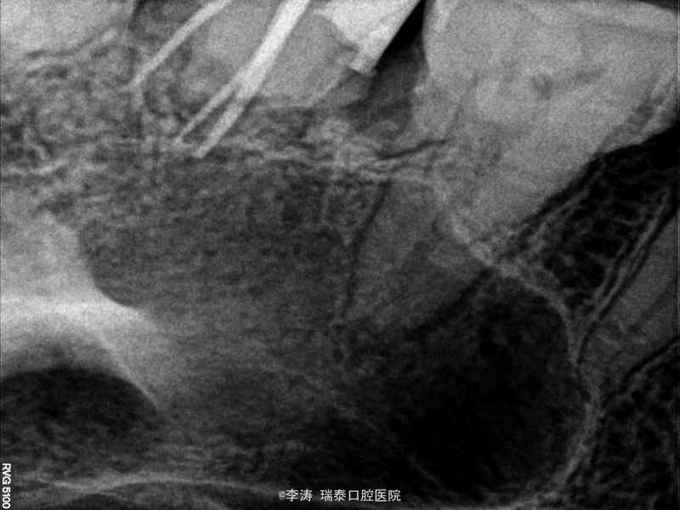

27牙伸长,松-,冷++,叩+-,近中邻面大面积龋坏,探及穿髓孔,x线片近中大面积龋坏近髓腔

27牙牙髓炎,行根管治疗 27磨短,测根长腭根11mm,近颊及远颊根15mm。置橡皮障,根管预备,根管消毒,根管充填。

1,关于伸长牙的修复问题,因为牙根比较短小,修复起来远期效果怎么样?伸长多少的牙齿需要拔掉呢?是没松动都可以修复吗? 2,后牙上橡皮障以后很难拍片子,所以本病例拍片的时候全是取下来的。不知道大家是怎么做的呢?